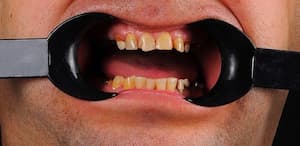

Нерівномірна патологічна стирання зубів, гіперфункції м'язів, відсутність зубів. Відновлення естетики та функціональності зубощелепного ряду верхньої та нижньої щелеп.

Виражений бруксизм, стирання зубів після гнатологічного обстеження лікар вирішив завищувати прикус до 2 мм і фіксацію центрального співвідношення. Встановлено коронки E.max на свої зуби. Коронки на імплантах виготовлені з металокераміки для запобігання сколам.